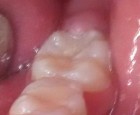

Bệnh nhân: Ng. Bá Tuấn Đ. 6 tuổi, răng 36, mã BA 6320/17

Sau sáu tháng. ICDAS: 2; Di: 21 | Sau chín tháng. ICDAS:1; Di: 19 | Sau 12 tháng. ICDAS: 1; Di: 14 |